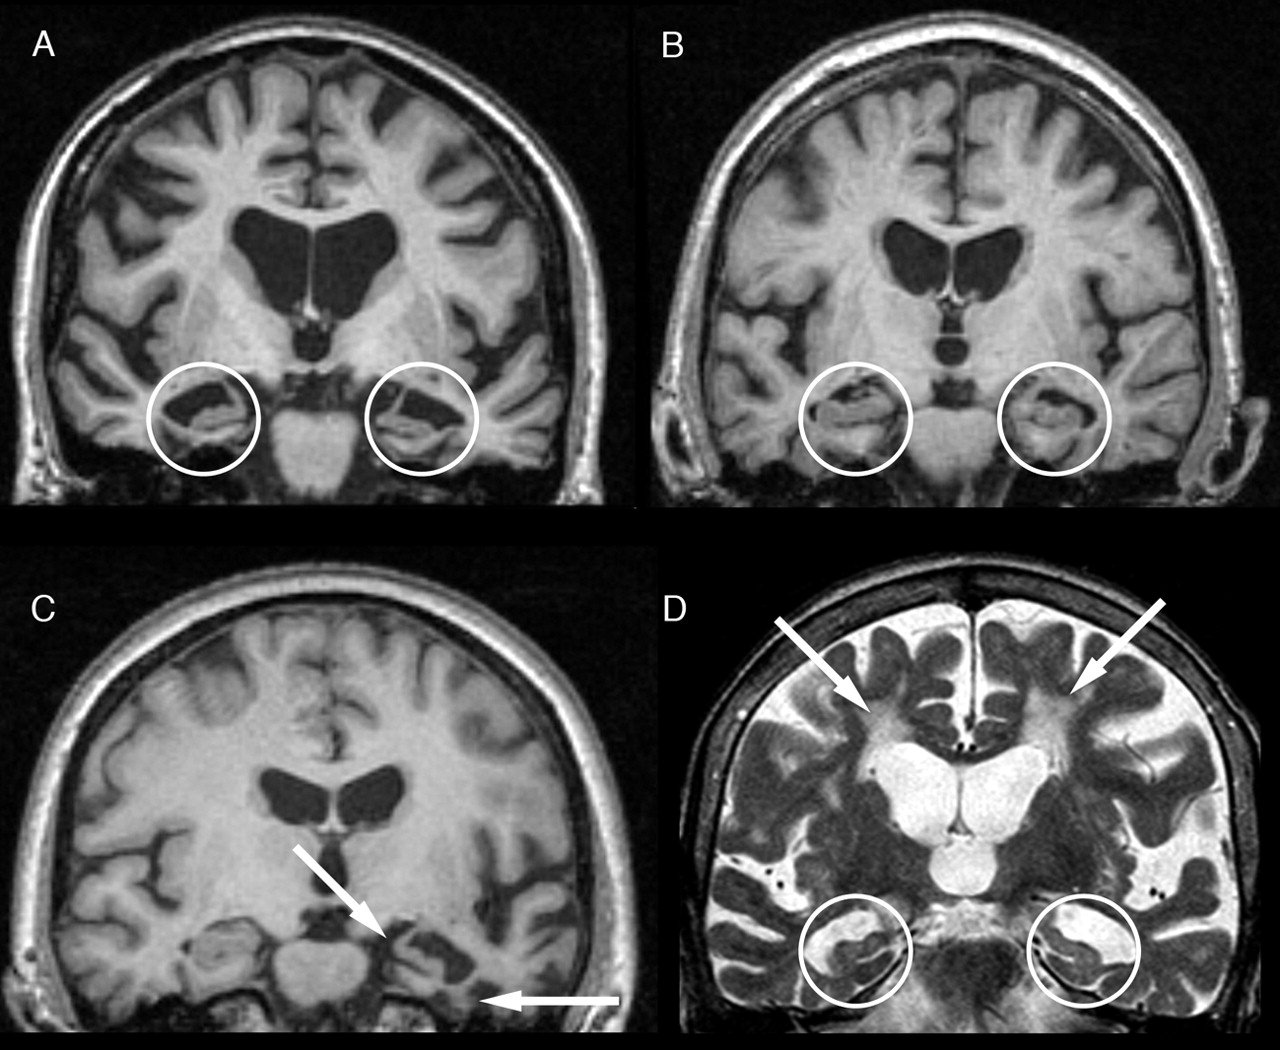

Representative Brain MRI Of Dementia Patients. A Patient A Was

www.researchgate.net

www.researchgate.net

dementia mri patients diagnosed publication vascular atrophy

mri dementia degeneration corticobasal cbd

MRI In Dementia | Radiology Key

radiologykey.com

radiologykey.com

dementia mri radiology